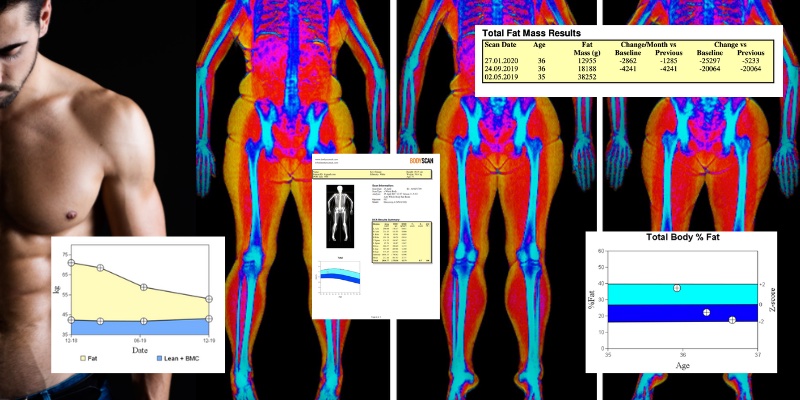

There are many ways of finding out your body composition but none are as effective as a body composition scan. The scan generates a ‘fat shadow’ image showing the fat distribution in the abdomen, arms, legs and pelvis. Not only does a DEXA scan provide fast results, but it is also widely accepted as the gold standard for obtaining a comprehensive analysis of body composition.

DEXA scans use two low-dose X-ray beams that pass through the body at different energy levels. By measuring the absorption of each beam by the body tissues, DEXA can differentiate between bone mineral content, fat tissue, and lean tissue (muscles, organs, etc.). The results are highly precise and provide a detailed breakdown of body composition.

The DEXA report is particularly accurate and detailed because the scan is able to differentiate between fat mass and lean muscle mass. This is crucial for understanding your true health and fitness levels. One of the most important findings is your visceral fat measurements.

The report breaks down your Total Body Composition (including the overall percentages and absolute amounts of body fat, lean tissue mass, and bone mineral content); Fat Mass (the total amount of body fat measured in grams or kilograms and its percentage relative to total body weight); Lean Mass (the total weight of lean tissue, which includes muscles, organs, and water, usually reported in grams or kilograms); Bone Mineral Content (BMC) (the weight of the minerals in bones, which helps assess bone health alongside body composition); and Regional Analysis (body composition measurements for different regions of the body to help identify specific areas with higher fat deposition or lean mass),

In addition to including your individual measurements, your DEXA scan report also includes percentile comparisons based on your age, and sex. These percentages indicate how the patient’s body composition compares to a reference population. Reference standards percentiles are based on population studies and reference data to help healthcare providers determine whether a person’s body composition is within a healthy range.

Getting the report showed my lean muscle mass across my entire body, with a detailed breakdown of every limb. Seeing whether my right and left leg were balanced, where I was holding onto any fat, and my skeletal health was been incredibly important. The scan has helped me adjust some nutrition elements as well as focus on other muscle areas in the gym that I wouldn’t have known about otherwise.